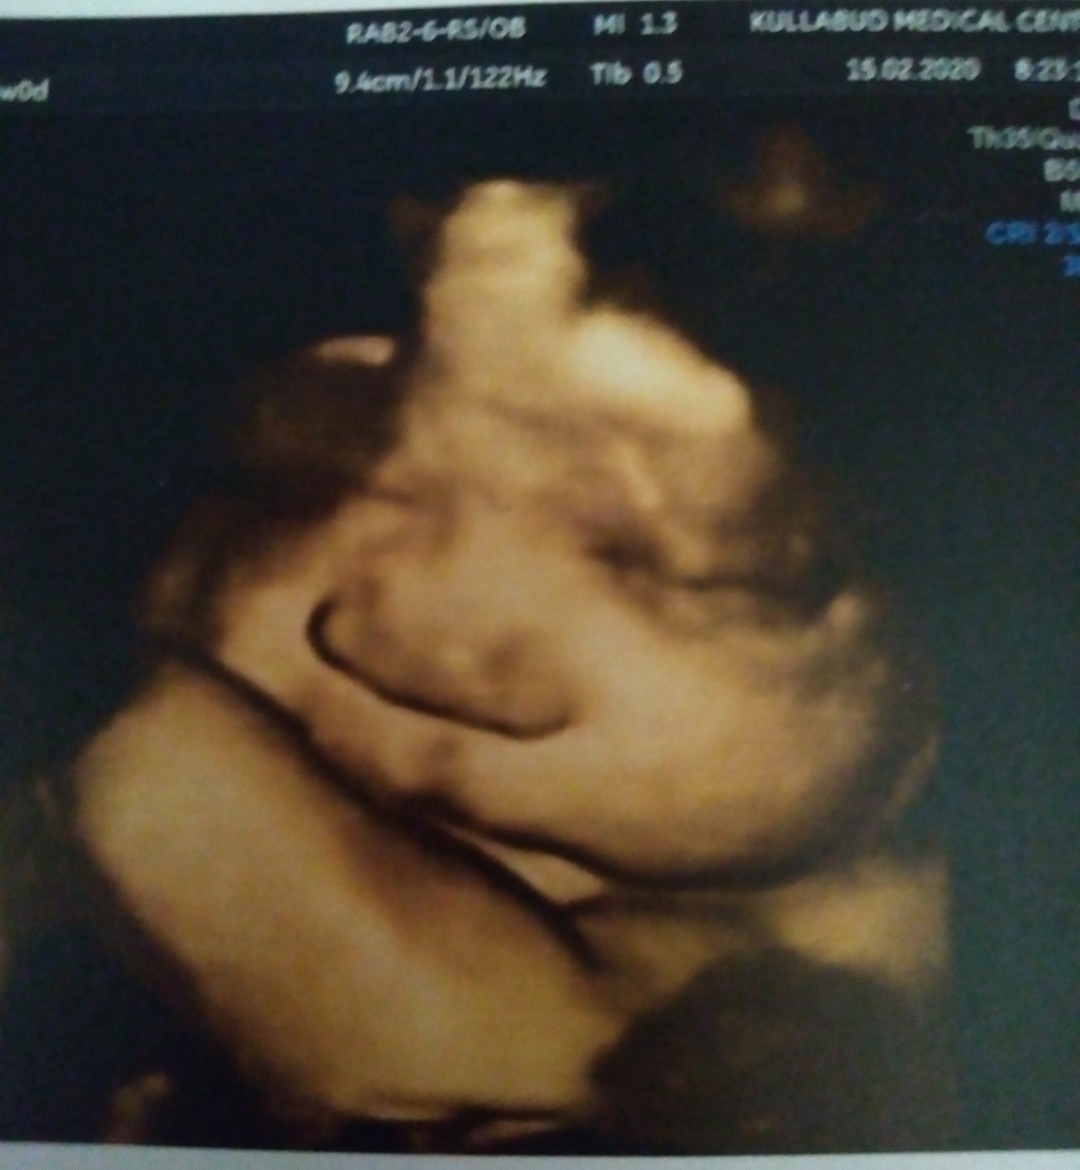

ตอน24wค่ะผู้ชายคุณหมอบอกหล่อหน้าตาดีคะ😂😂😂